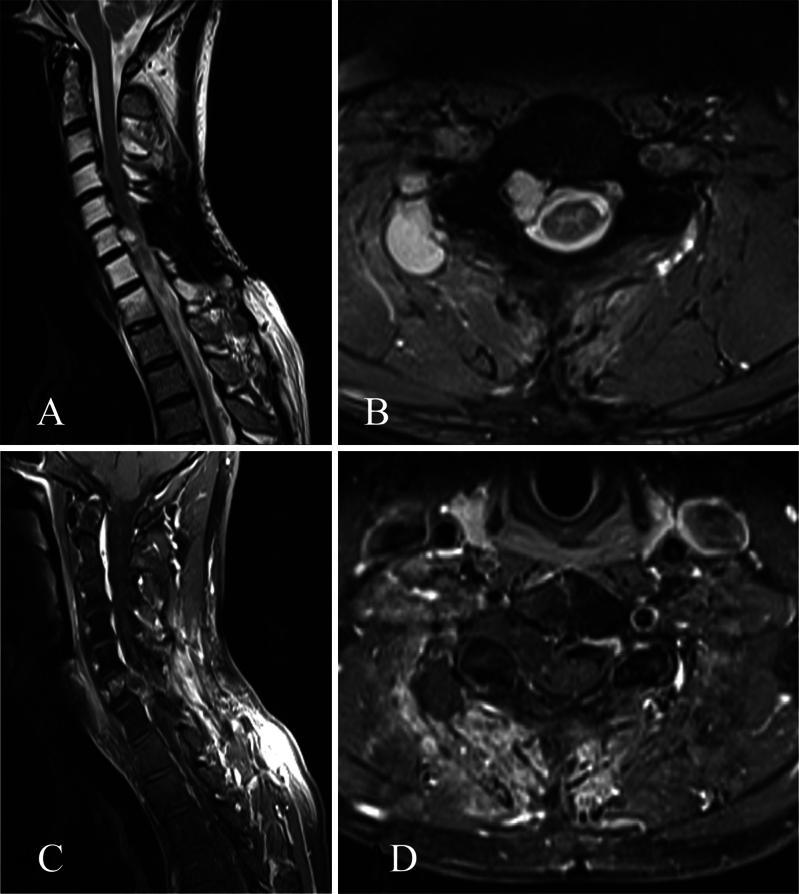

Background: Chondrosarcomas are rare malignancies arising from the bone, primarily from the mobile spine. Multimodal treatment is the standard of care, with surgery as a cornerstone for local control since incomplete resection is the main driving factor for progression and disease-related mortality.

Observations: Here, the authors present the case of a patient who underwent an initial subtotal resection and adjuvant proton beam radiation therapy. Subsequent salvage surgery with aggressive resection was planned in an interdisciplinary setting, resulting in complete resection without recurrence. Despite incomplete resection initially, this case represents an example for reconsidering salvage surgery in an interdisciplinary setting and center of expertise even for cases with residual tumor burden.